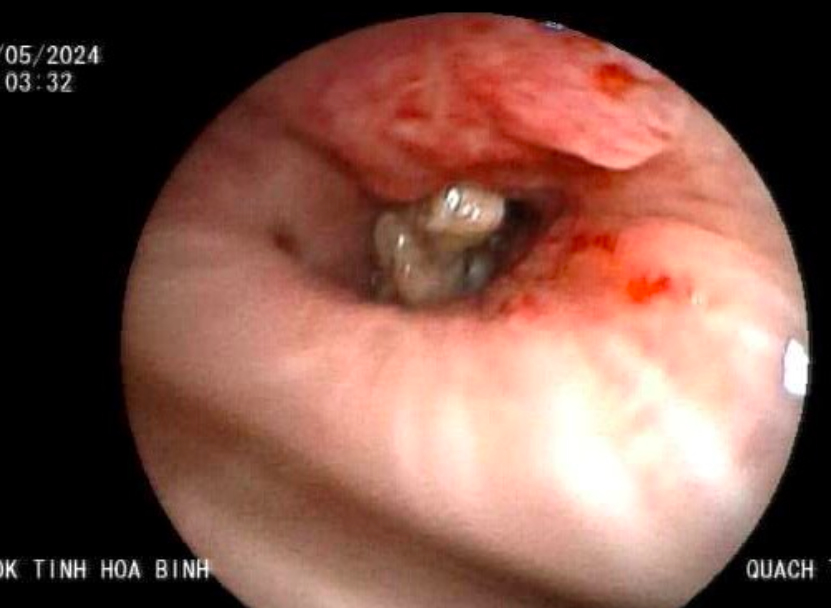

"Khi đưa ống nội soi đến phế quản thùy dưới phổi trái, thầy thuốc phát hiện một dị vật to bằng đầu ngón tay út, có nhiều góc cạnh, đờm và mủ bao phủ bên ngoài", Tiến sĩ, bác sĩ Hoàng Công Tình, Trưởng khoa Hồi sức tích cực 1 của bệnh viện, cho biết.

Dị vật chắn ngang phế quản làm cản trở thông khí của thùy dưới phổi trái, kèm theo hoá mủ và áp xe hóa. Ngoài ra, dị vật di động theo nhịp thở, cọ vào thành phế quản gây chảy máu.